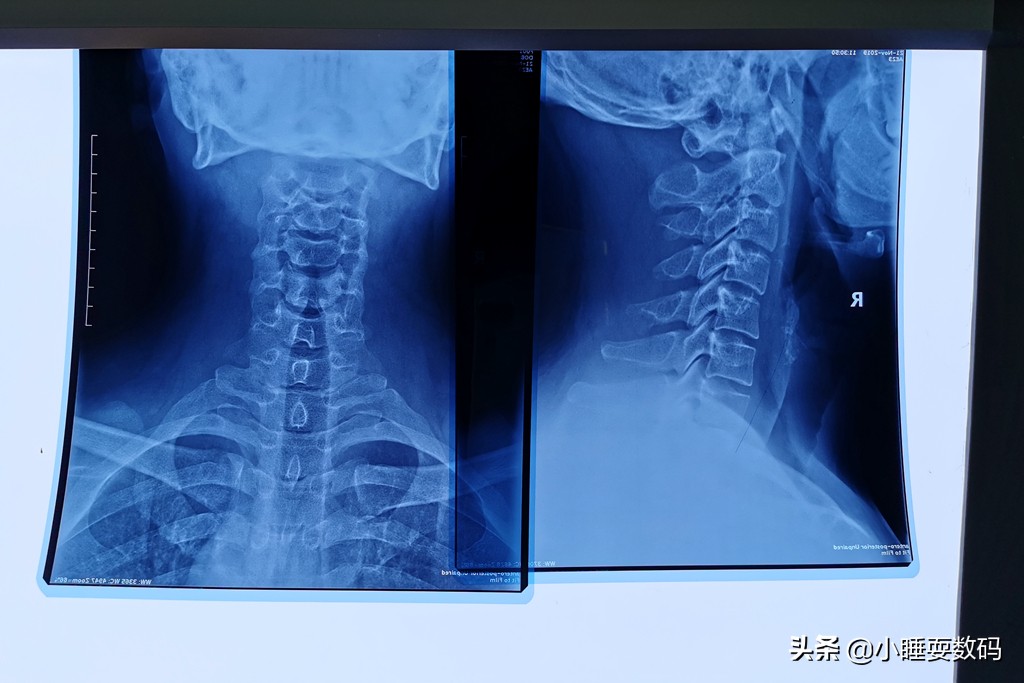

小睡本人也是一名颈椎病患者,工作上需要长期面对电脑,加上自己没有关注保养,久而久之也发展成了颈椎病。前几天甚至出现了头晕、乏力的症状,到医院拍了CT片子检查,颈椎的生理弧度几乎完全消失了,从上面的图片可以明显的看到。从医院开了药、买了牵引矫正器材,医生还叮嘱说睡觉不要枕太高的枕头睡觉,这是为什么呢?因为枕太高的枕头,脖子的姿势就相当于白天低头看手机。

再测评之前还是要普及一下,到底什么才是对颈椎好的枕头?我们都知道人体正常的颈椎应该是有一个向前的弧度,像弯弯的香蕉一样,可以增加颈椎弹性,保护头部。但如果睡觉枕的枕头太高,仰睡的时候效果就像我们白天玩手机低头一样,慢慢的颈椎就会变直。同样枕头太低的话,我们侧睡时,头部就会失去支撑,肩膀受压颈椎侧弯……因此颈椎病的形成和枕头的高低、睡觉的姿势都有关系,通过上面两幅图大家可以直观的感受到。